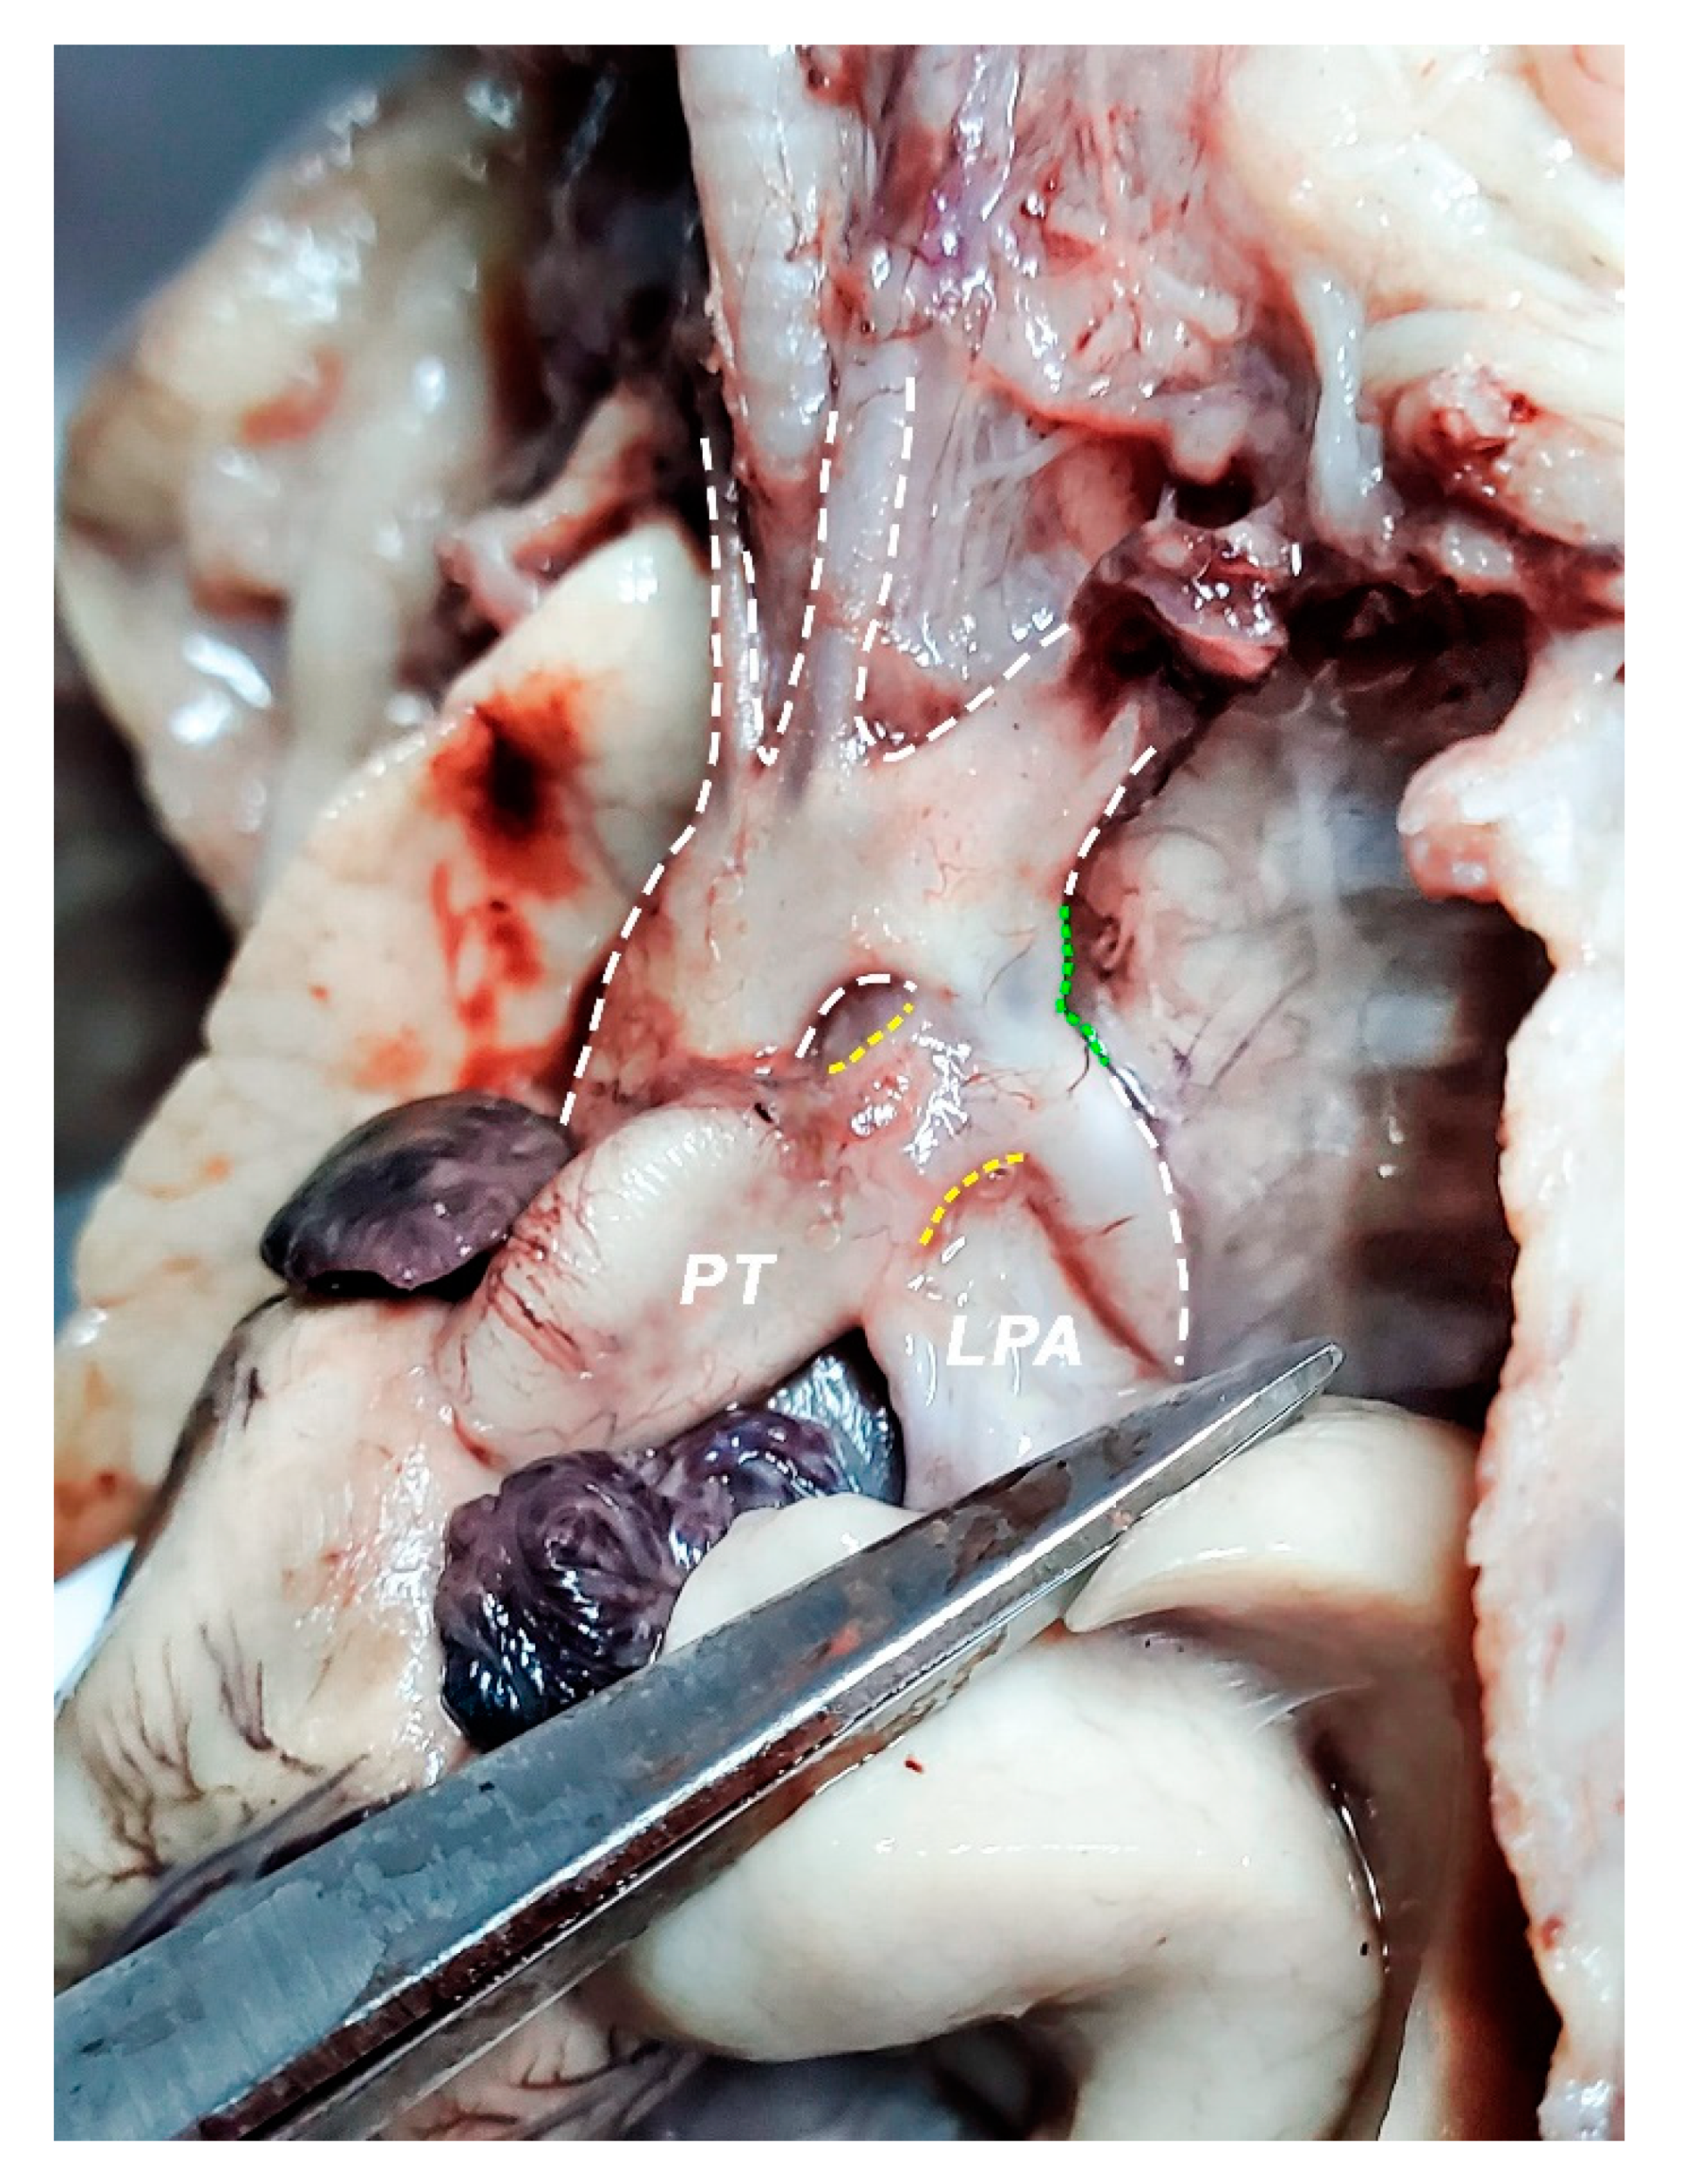

2.2. Dissection